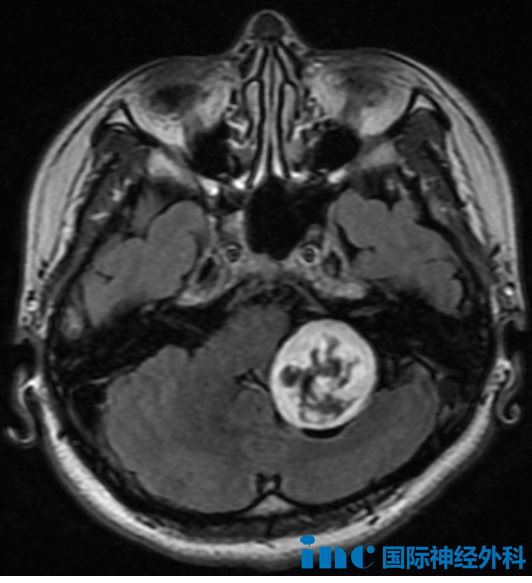

10月中旬,一次头颅检查,揭开了异常信号的真相:脑桥后方异常信号,约1.8cm×1.0cm,疑为脑实质肿瘤,胶质瘤可能。

第二,目前肿瘤在脑干内浸润尚浅。从影像看,它位于第四脑室表面,未深入脑干。但如果继续等待,肿瘤会向深处进展,大大增加手术难度。